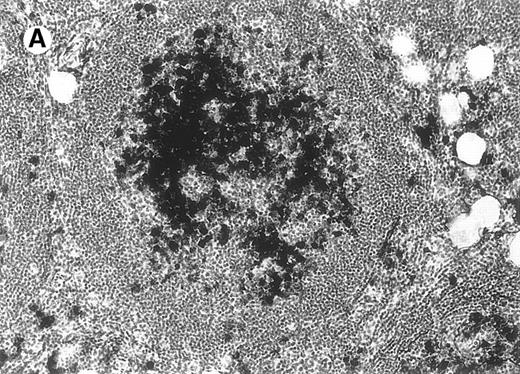

Neoplastic follicles.

The follicles lack a normal mantle zone and reveal nearly complete absence of tingible body macrophages (patient 9).

All cases of follicular lymphoma were classified as grade 2 according to the REAL classification. Histology showed bottom-heavy lymphoid infiltrates with prominent follicular pattern (Figures3 and 4). A well-formed mantle zone around most follicles was present only in 2 patients. In the other specimens the mantle zone was either reduced (11 patients) or nearly absent (2 patients) (Figure5). A clear-cut marginal zone was never observed. Tingible body macrophages within follicles were present only in 1 patient and were absent in the other 14 patients. Cytomorphology of follicles in all patients showed variable proportions of centrocytes (cleaved follicle center cells) and centroblasts (Figure6). The interfollicular areas revealed the presence of small lymphocytes and histiocytes admixed with a few larger cells and occasionally other inflammatory cells such as eosinophils and plasma cells.